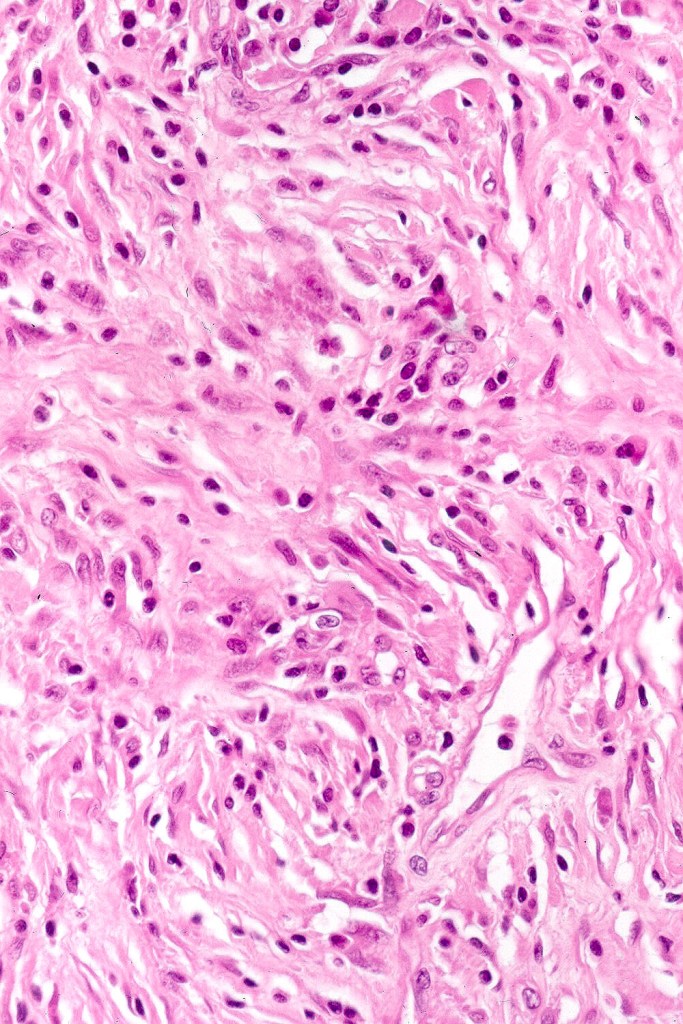

Histologically, it is characterized by a dense population of spindled, dendritic melnanocytes & melanophages with variable fibrosis. It may sometimes represent a component of a combined nevus. Mitotic activity is not usually present and pleomorphism is absent (see atypical blue nevus below). Involvement of the arrector pili muscle is not uncommon.

•Admixture of spindle cells, pigmented bipolar or dendritic cells & melanophages

•Cytoplasm is pale and nuclei are small with inconspicuous nucleoli

•An alveolar pattern is characteristic particularly with clear cell nodules

•Multinucleate giant cells sometimes present

•Stromal fibrosis, myxoid change, vascular hyalinization with cyst formation are often seen

•Some tumors are composed spindle cells in a fascicular or neuronevoid pattern